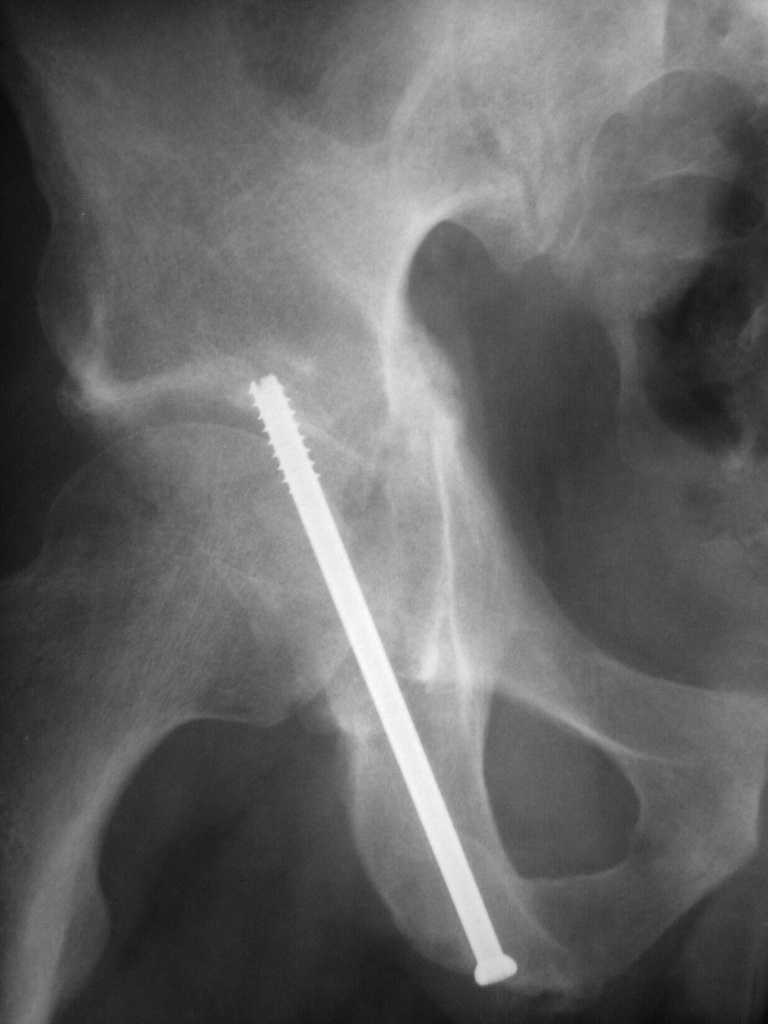

Yordan! In this case position of bone fragments is quite good. We

prefer to use miniinvasive technique. We fix posterior column by can.

screw and put 3mm pin with distal thread to the anterior column. Next day after

the surgery he may start walking with crutches.   3 month after the

surgery  we remove the pin.  In cases of maleolar fractures  we use

angle stable plates to lat. mal. and pins or screws and if

syndesmosis is intact - full loading is not forbidden.

Sending exampl pict.

Вложение не в текстовом формате было извлечено…

Имя     : 3.jpg

Размер  : 35084 байтов

Url     : http://weborto.net:8080/pipermail/ortho/attachments/20081205/95456be3/attachment-0005.jpg